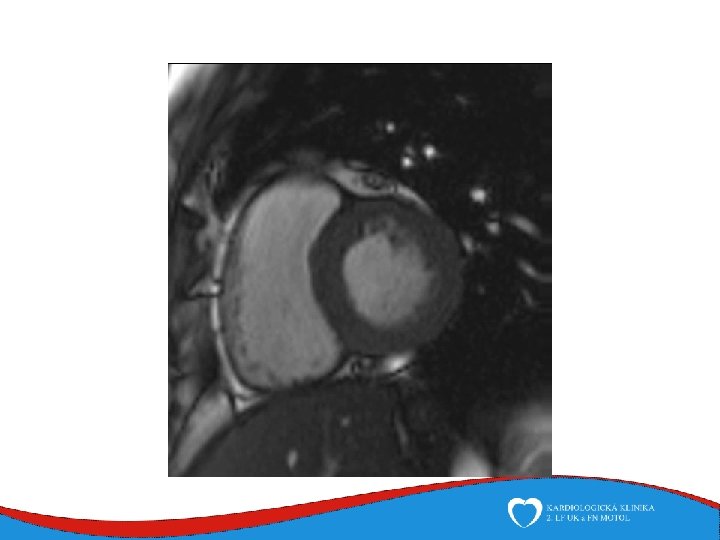

Work up ECG – typical - epsilon, neg. T v V 1 -V 3 - LBBB morphology VES ECHO MRI EMB